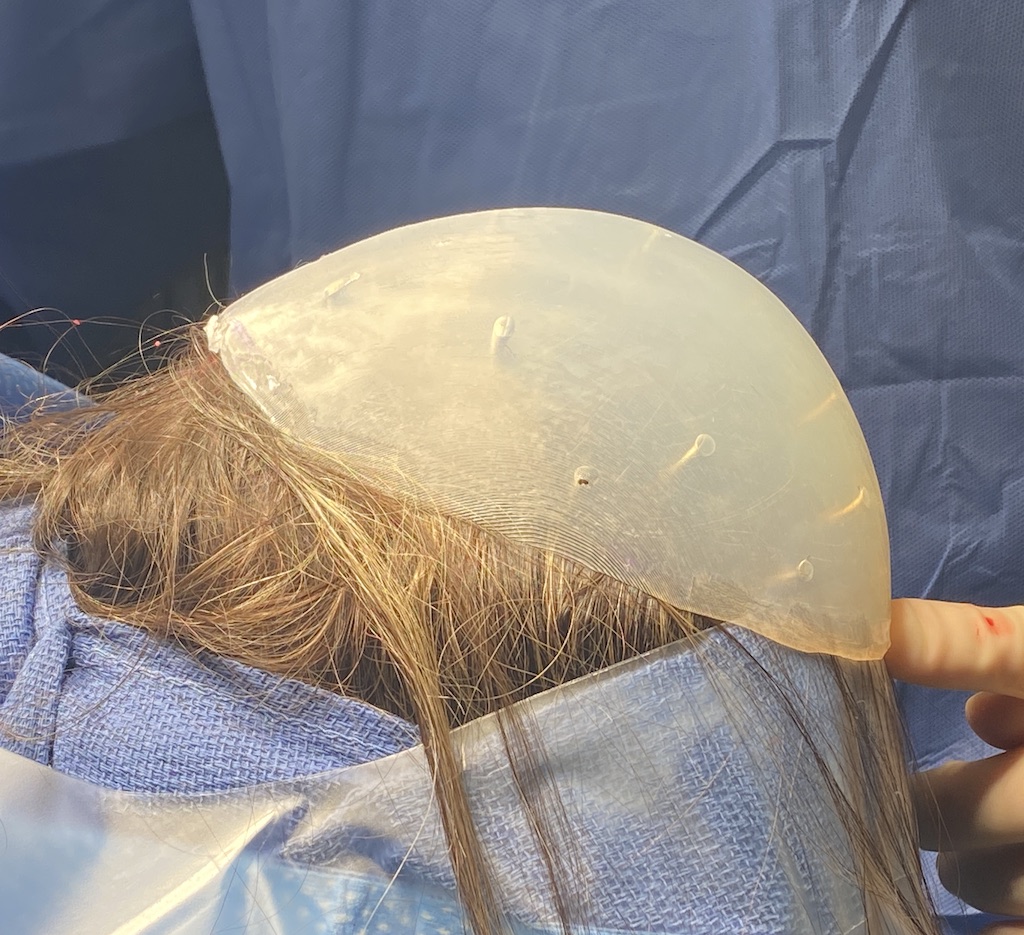

Desire for large skull augmentation for peanut-sized head, lifelong aesthetic concern.

Two stage skull augmentation with a first stage scalp tissue expansion and second stage two-piece custom skull implant.